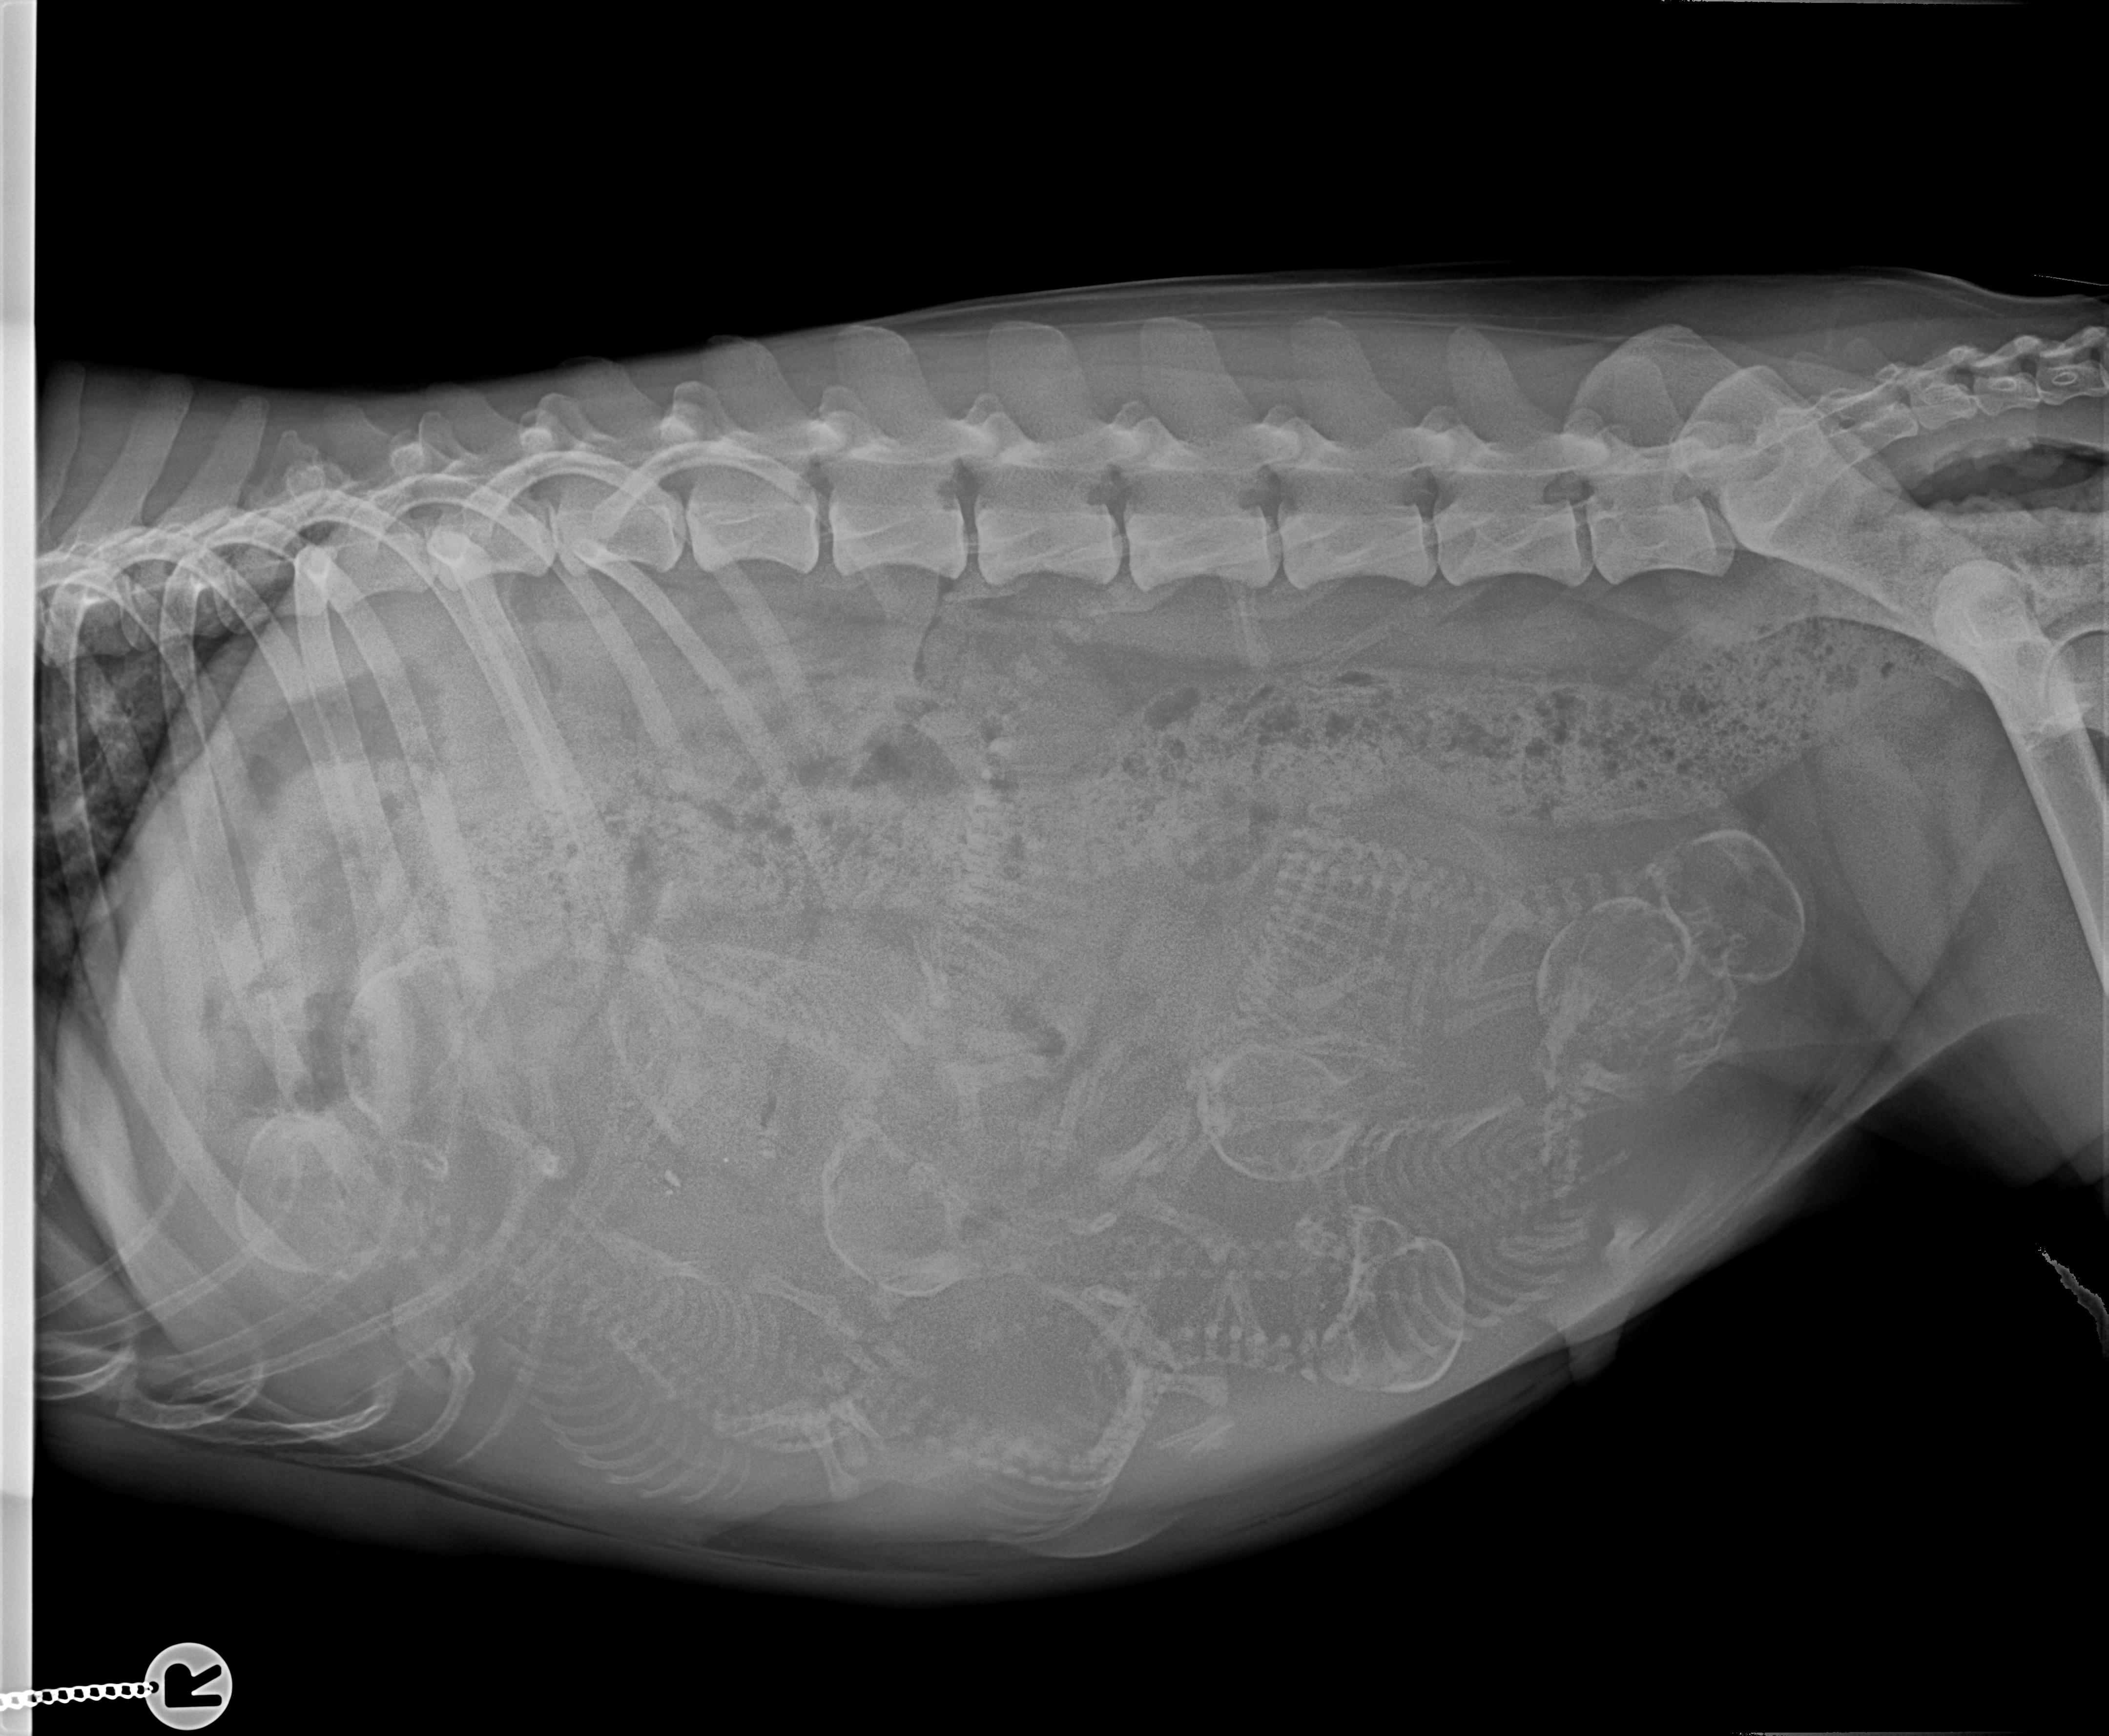

19.03.2018 57. TT |

Juhu... alles super bei der werdenden

Mama und die Zählung ergab 7 Zwerge *freu freu*

18.03.2018 56. TT |

Endspurt... Ab Montag können die Welpen fertig auf die Welt purzeln :o)) natürlich können sie noch ein bisschen warten. Wir fahren morgen noch mal zum Tierarzt alles abchecken und Röntgen, damit wir wissen wie die kleinen Hampelmänner liegen und wie viele es genau werden. Sie strampeln schon kräftig und der werdenden Mama geht es so super das man noch im Schnee rum springt. Heute füge ich die Temperaturtabelle ein und morgen wird die Wurfbox vorbereitet... dann sitzen wir täglich in den Startlöchern. Zu Erklärung: Da wir uns dem Ende der Trächtigkeit nähern, kann es ja täglich los gehen und natürlich überprüfen wir mehrmals am Tag die Temperatur von Romy. Denn wenn sie 1 Grad unter ihrer normalen Temperatur fällt, erwarten wir in 12- 24 Std. nach dem Temperaturabfall die Welpen. So können wir hier nix verpassen und ihr könnt an der Tabelle sehen wenn es los geht, die Geburt wird wie gewohnt hier mitgeschrieben! |